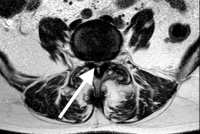

Arachnoiditis is actually the inflammation of the arachnoid membrane. The nerves are coated by this membrane within the CSF and inflammation can cause scarring and the nerves to “stick together” in clumps. Interestingly enough- like many conditions of the spine, some people have this condition and never develop symptoms.

The pathology of arachnoiditis of the lumbar spine is that the small spider web connections scar, contract and stick the nerves together. This reduces the nerve membrane exposure to the CSF and injures the small blood vessels that line and feed these nerves. This lack of blood circulation and the direct scar injury to the nerve can cause chronic nerve discharge or blocked signals. The nerves also don’t move normally when scarred. A normal nerve moves back and forth in the canal up to an inch when the leg is flexed or extended just like a cable over a pulley. If the nerve is tethered, it can’t stretch and the mechanical deformation with movement can cause symptoms.